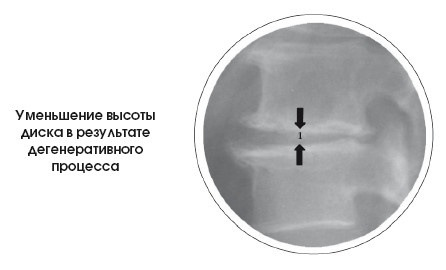

Дегенерация диска – это повреждение структуры межпозвоночных дисков (снижение эластичности и появление трещин и щелей) и потеря дисков в высоте (1) из-за прогрессирующей дегидратации. Она рассматривается как часть процесса старения.

Защемление диска (2) – это захват дисков прилежащими костными структурами (тела позвонков), приводящий к потере высоты дисков.